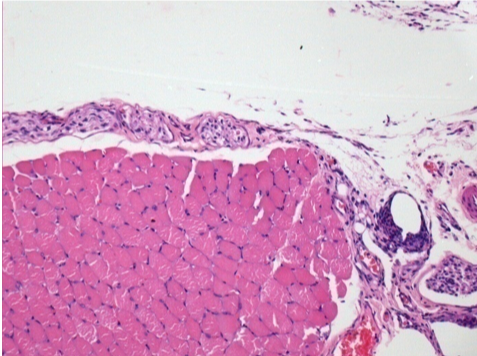

Control

Comment : Nothing to declare after saline solution injection

L:Pretibial-No treatment

R:Pretibial-After 0.1 ml NaCl 0.9% IM